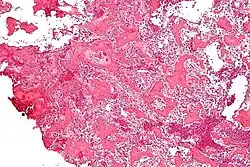

À l'examen histologique, l'ostéome ostéoïde présente :

- un petit (< 1,5–2 cm), nidus jaunâtre à rouge d'os tissé avec des trabécules interconnectées

- un fond et un bord de tissu conjonctif fibreux hautement vascularisé.

Des degrés variables de réaction osseuse sclérotique peuvent entourer la lésion. L'ostéoblastome bénin est pratiquement indiscernable de l'ostéome ostéoïde.

L'aspect habituel présente un stroma fibrovasculaire avec de nombreux ostéoblastes, du tissu ostéoïde, de l'os tissé bien formé et des cellules géantes. Les ostéoblastes étaient généralement petits et de forme régulière[2].